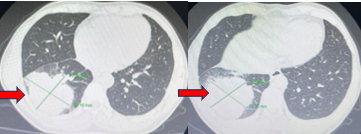

Cắt lớp vi tính lồng ngực (5/4/2019):

Hình 3:  Hình ảnh khối u thuỳ dưới Phổi phải, kích thước 70×75 mm (mũi tên đỏ) nhiều tổn thương thứ phát 2 phổi, hạch trung thất và rốn phổi phải (mũi tên vàng)